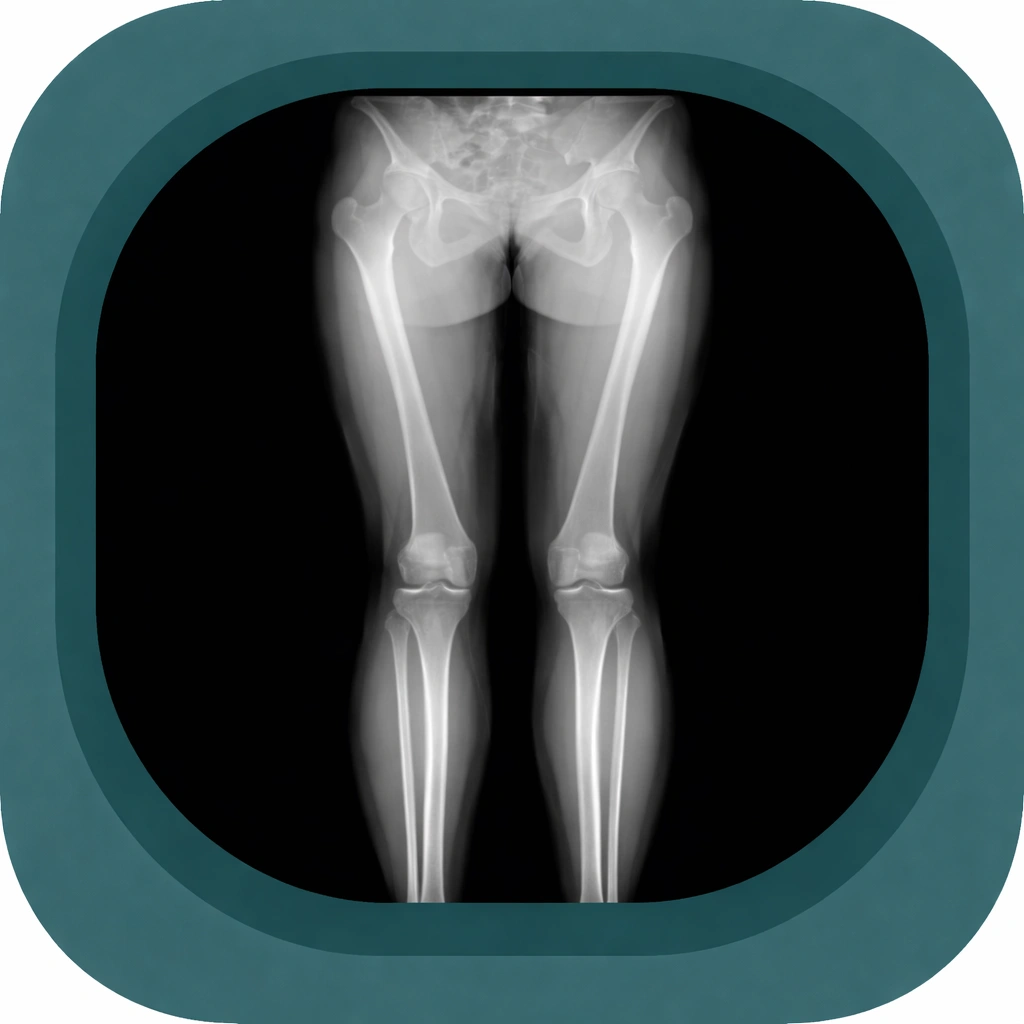

Explore high-quality X-ray anatomy from head to toe. Our database features carefully labelled images to visualize fine structures—perfect for radiologists, students, and surgeons.